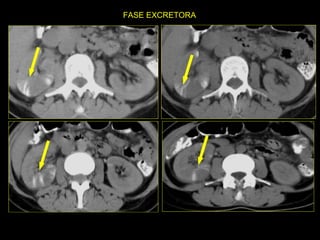

Caso # 7 ♀ , 45 años,  dolor abdominal difuso, sin poder determinarse la causa clínicamente por lo que se envía a TC para búsqueda de la probable causa de dolor. Estudio en fases arterial, venosa y excretora, mostrándose cortes axiales.

FASE EXCRETORA

Hallazgos Caso # 7: Hay un área triangular de disminución de la atenuación en la parte posterolateral del  riñón izquierdo, las cuales se demuestran en fases contrastadas, y en fase excretora muestran persistencia del medio de contraste, en relación con proceso inflamatorio focal.